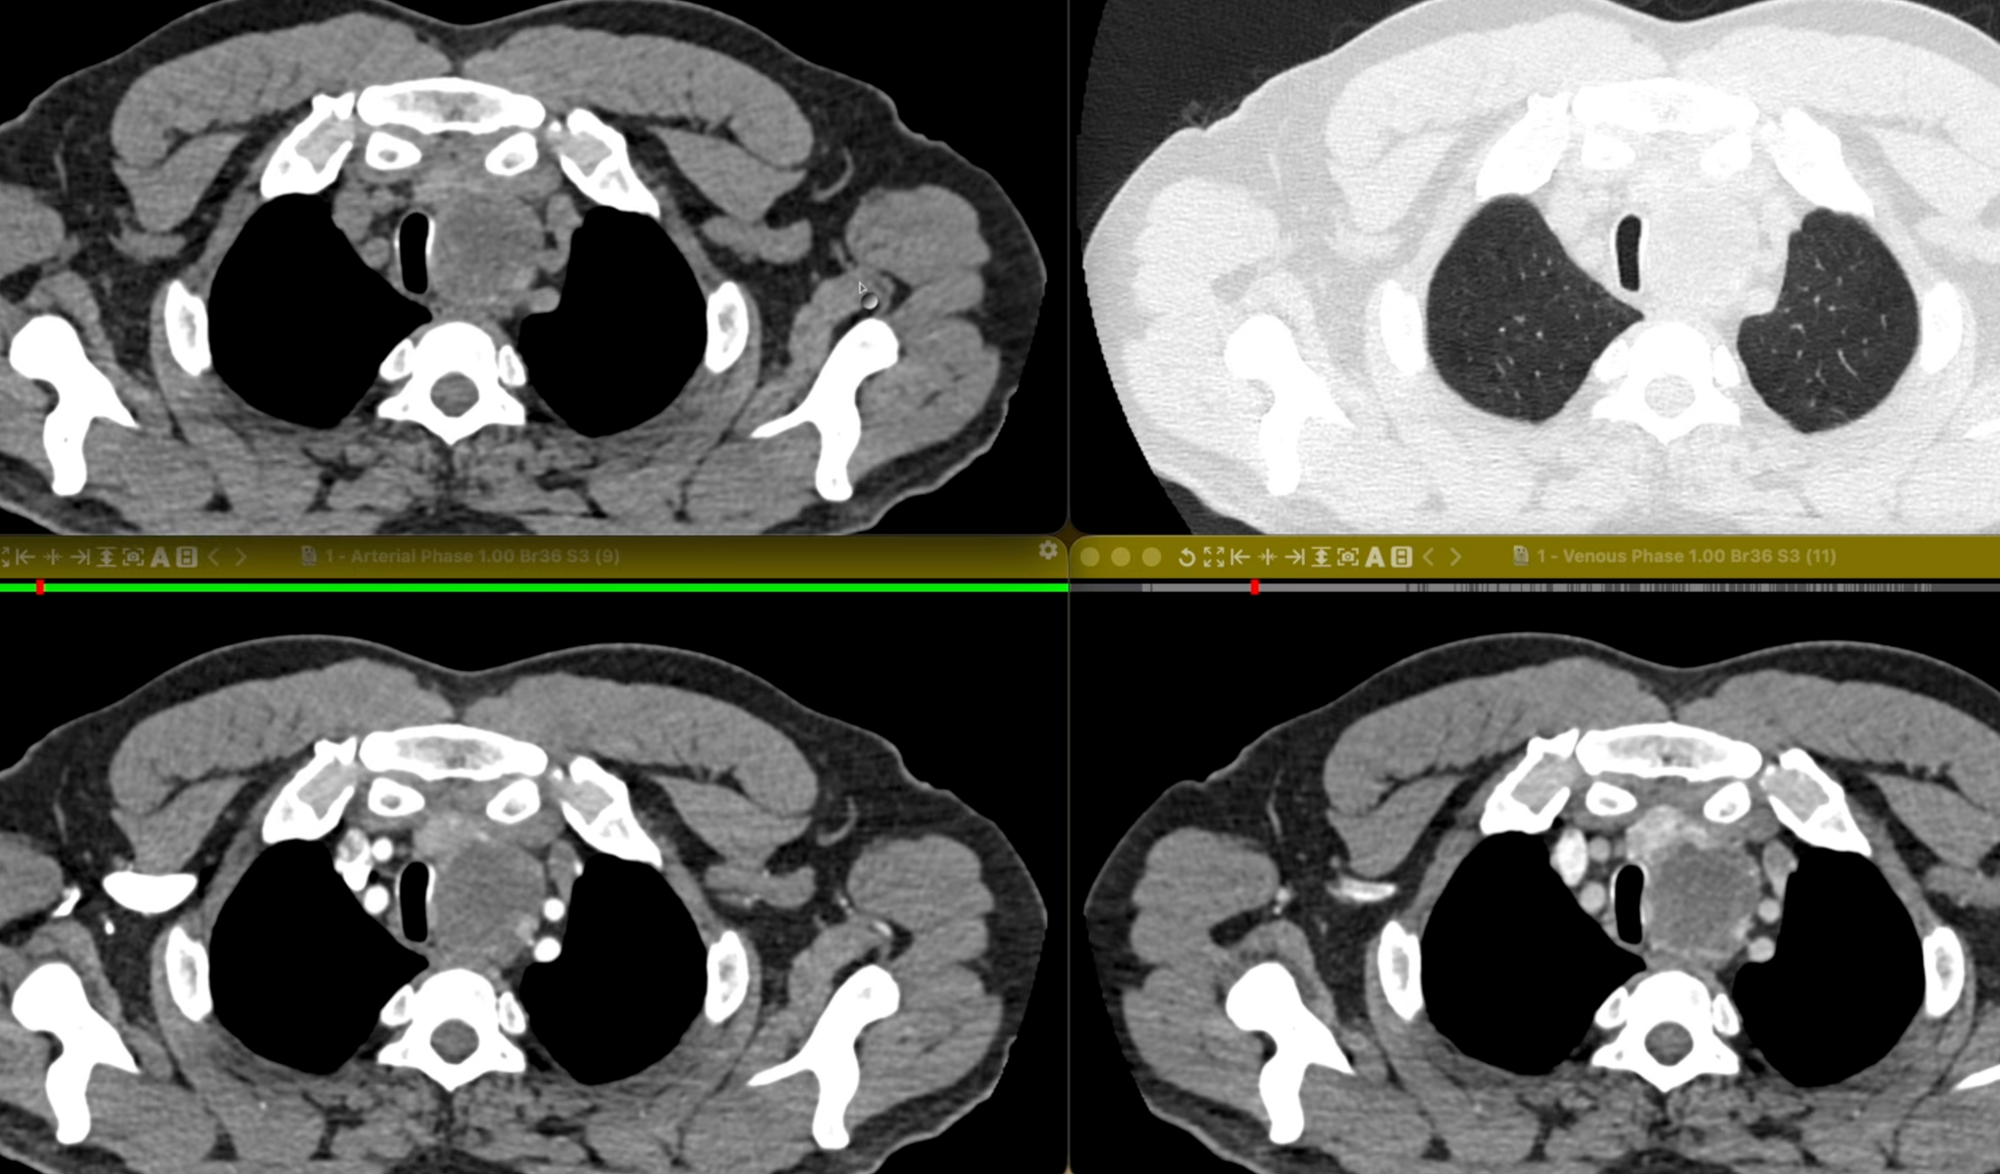

COD 185 - Visceral Mediastinal Mass

48-years old smoker with moderate centrilobular emphysema presents with a mediastinal mass.

- Thymoma

- Lymphoma

- Thyroid lesion

- Necrotic malignantcy

- Necrotic TB node